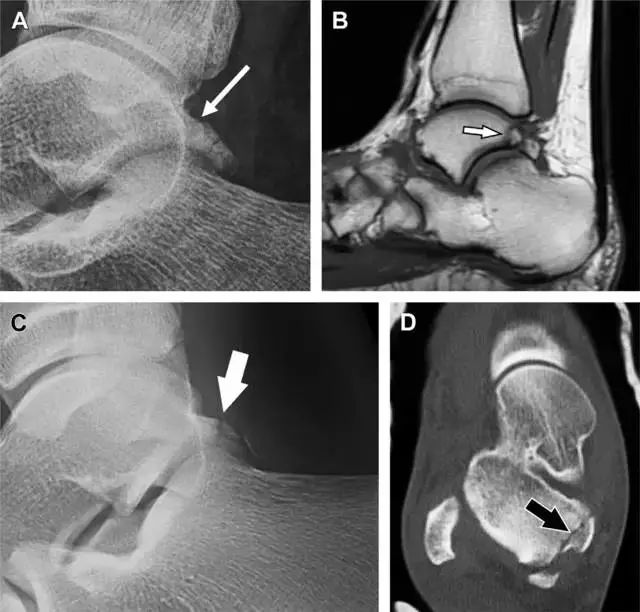

20

跟骨前突骨折

呈 Y 形的分歧韧带附着于跟骨前突上,是维持踝关节跖屈和背屈稳定性的重要结构。跟骨前突骨折常发生于足跖屈内旋、分歧韧带被牵拉时,或者足背屈外旋、骰骨和距骨挤压前突时。而这些骨折在初次 X 线检查时常常被漏诊掉。踝部侧位片诊断这些骨折最佳,准确诊断的关键点在于,必须仔细查看是否存在骨皮质中断(图 6)。如果侧位片可疑,建议加做斜位片协助诊断。

图 6 跟骨前突骨折。A 侧位片示跟骨前突骨折(箭头),与舟骨的重叠使骨折显示模糊;B 另一位患者的侧位片示内翻损伤所致的骨折(箭头),这种损伤机制引起小块的骨折。

21

趾短伸肌跟骨撕脱性骨折

另一种重要的跟骨撕脱性骨折,于足内翻时发生在趾短伸肌的起点处。观察来自跟骨背外侧的、不同大小的骨折块,前后位 X 片最适合不过了(图 7)。

图 7 溜冰受伤的患者,趾短伸肌跟骨撕脱性骨折。正位片示 2 个骨折块(箭头)来源于跟骨前外侧、趾短伸肌的起点处。踝关节外侧远端是否存在软组织水肿是一个重点观察点。